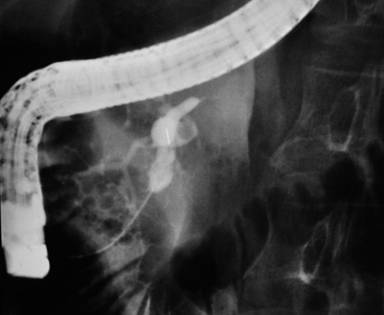

Since the pancreatic fistula failed to close after 3 months of watchful management, endoscopic retrograde cholangiopancreatography (ERCP) with a therapeutic intent of transpapillary stenting was performed. The same showed ductal disruption at the genu. A transpapillary stent was placed but the defect could not be bridged. After transpapillary stenting, although he had a transient reduction in fistula output, closure of the fistula did not occur. ERCP was repeated one month later which showed a complete cut-off of the pancreatic duct at genu with failure to cannulate the distal (upstream) duct (Figure 2). A faint streak of contrast extravasation was seen. With the failure of the endoscopic therapy, a diagnosis of “disconnected duct syndrome” was made and surgery planned. Computed tomography fistulography was performed to define the ductal anatomy, but it was not informative.

Figure 2. Endoscopic retrograde pancreatography carried out 4 months after external drainage shows complete ductal obstruction at genu with failure to cannulate the upstream pancreatic duct. |